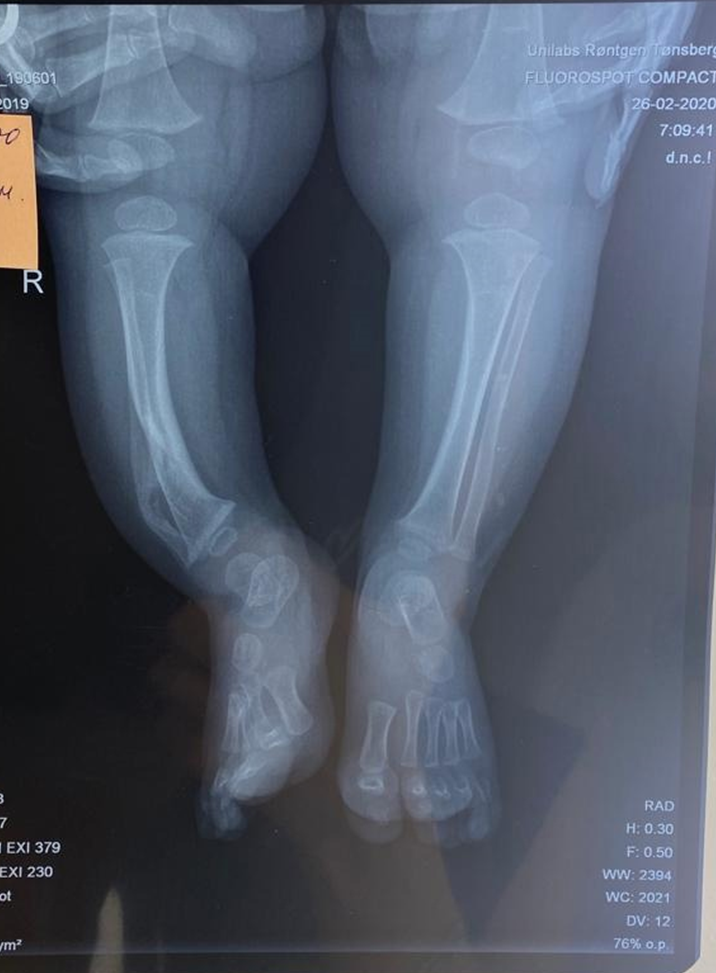

В семье абсолютно здоровых родителей появился замечательный здоровый мальчик, у которого до 6 месяцев было все хорошо. Но затем его правая ножка в районе голени стала искривляться. Кости голени справа оказались не до конца сформированными, и наша самая прочная кость – большеберцовая – оказалась не опороспособной. Мальчику была показана высокотехнологичная медицинская помощь в г. Санкт – Петербург. В институте имени Г.И.Турнера Мише провели пластическую операцию на костях, тот участок кости, который отсутствовал, заменили аллотрансплантатом (костным порошком). Если отстраниться от этого случая, то подобные деформации лечатся очень тяжело и успешность операции зависит в первую очередь от ее своевременности. Так, по данным литературы, 50 % детей с подобными проблемами становятся инвалидами, конечность остается не опороспособной, укорачивается, утрачивается навык ходьбы, развивается сколиоз и ребенок садится в инвалидное кресло.

Но случай с данным малышом – это крайняя заинтересованность родителей в своевременности получении ВМП и соблюдение всех рекомендаций ортопеда. Прошло 4 года после оперативного вмешательства – нога опороспособна, движения в суставах в полном объеме, укорочения голени и деформации стопы нет, изменения осанки нет, а также у ребенка есть возможность самостоятельного передвижения. Он ничем не отличается от сверстников, носит мягкий ортез, чтобы не давать излишней нагрузки на сустав.

На снимке в прямой проекции отмечается деформация (искривление) и укорочение костей правой голени (до операции)

Сразу после операции (2020) и спустя 4 года (2023) – деформации практически не видно